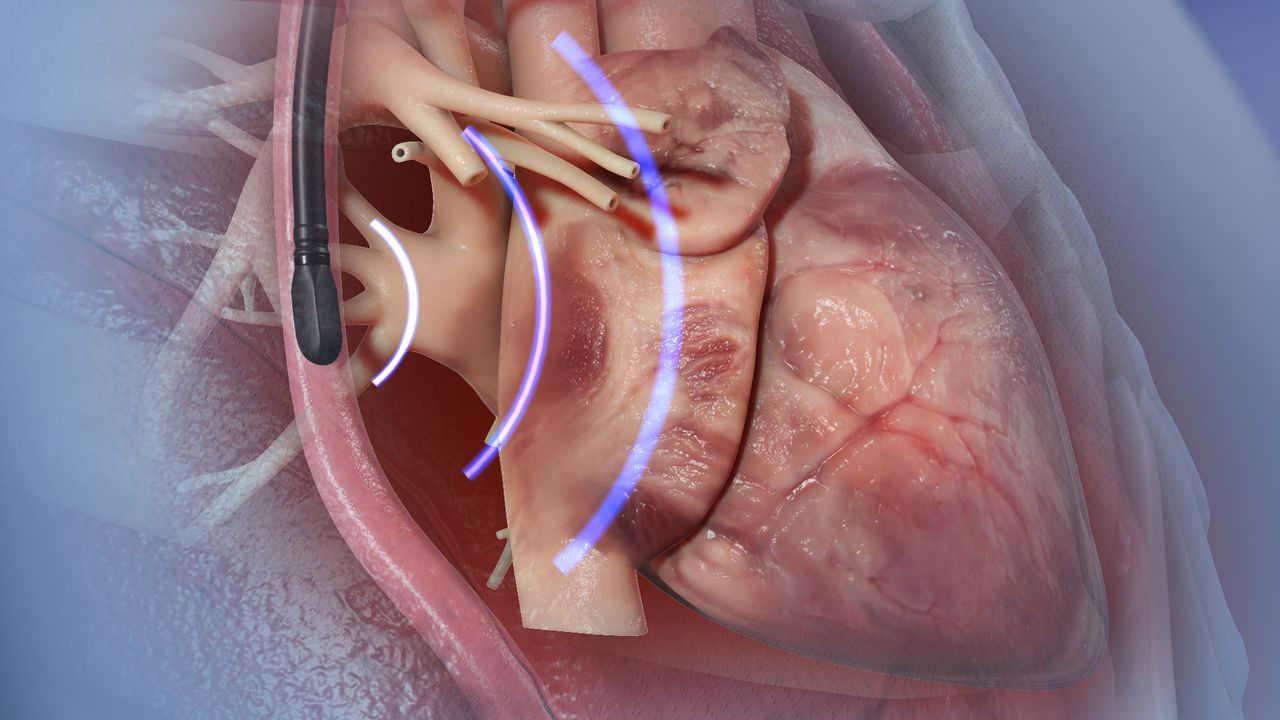

Read MoreEchocardiography

Echocardiography is a non-invasive imaging technique that uses ultrasound waves to create …